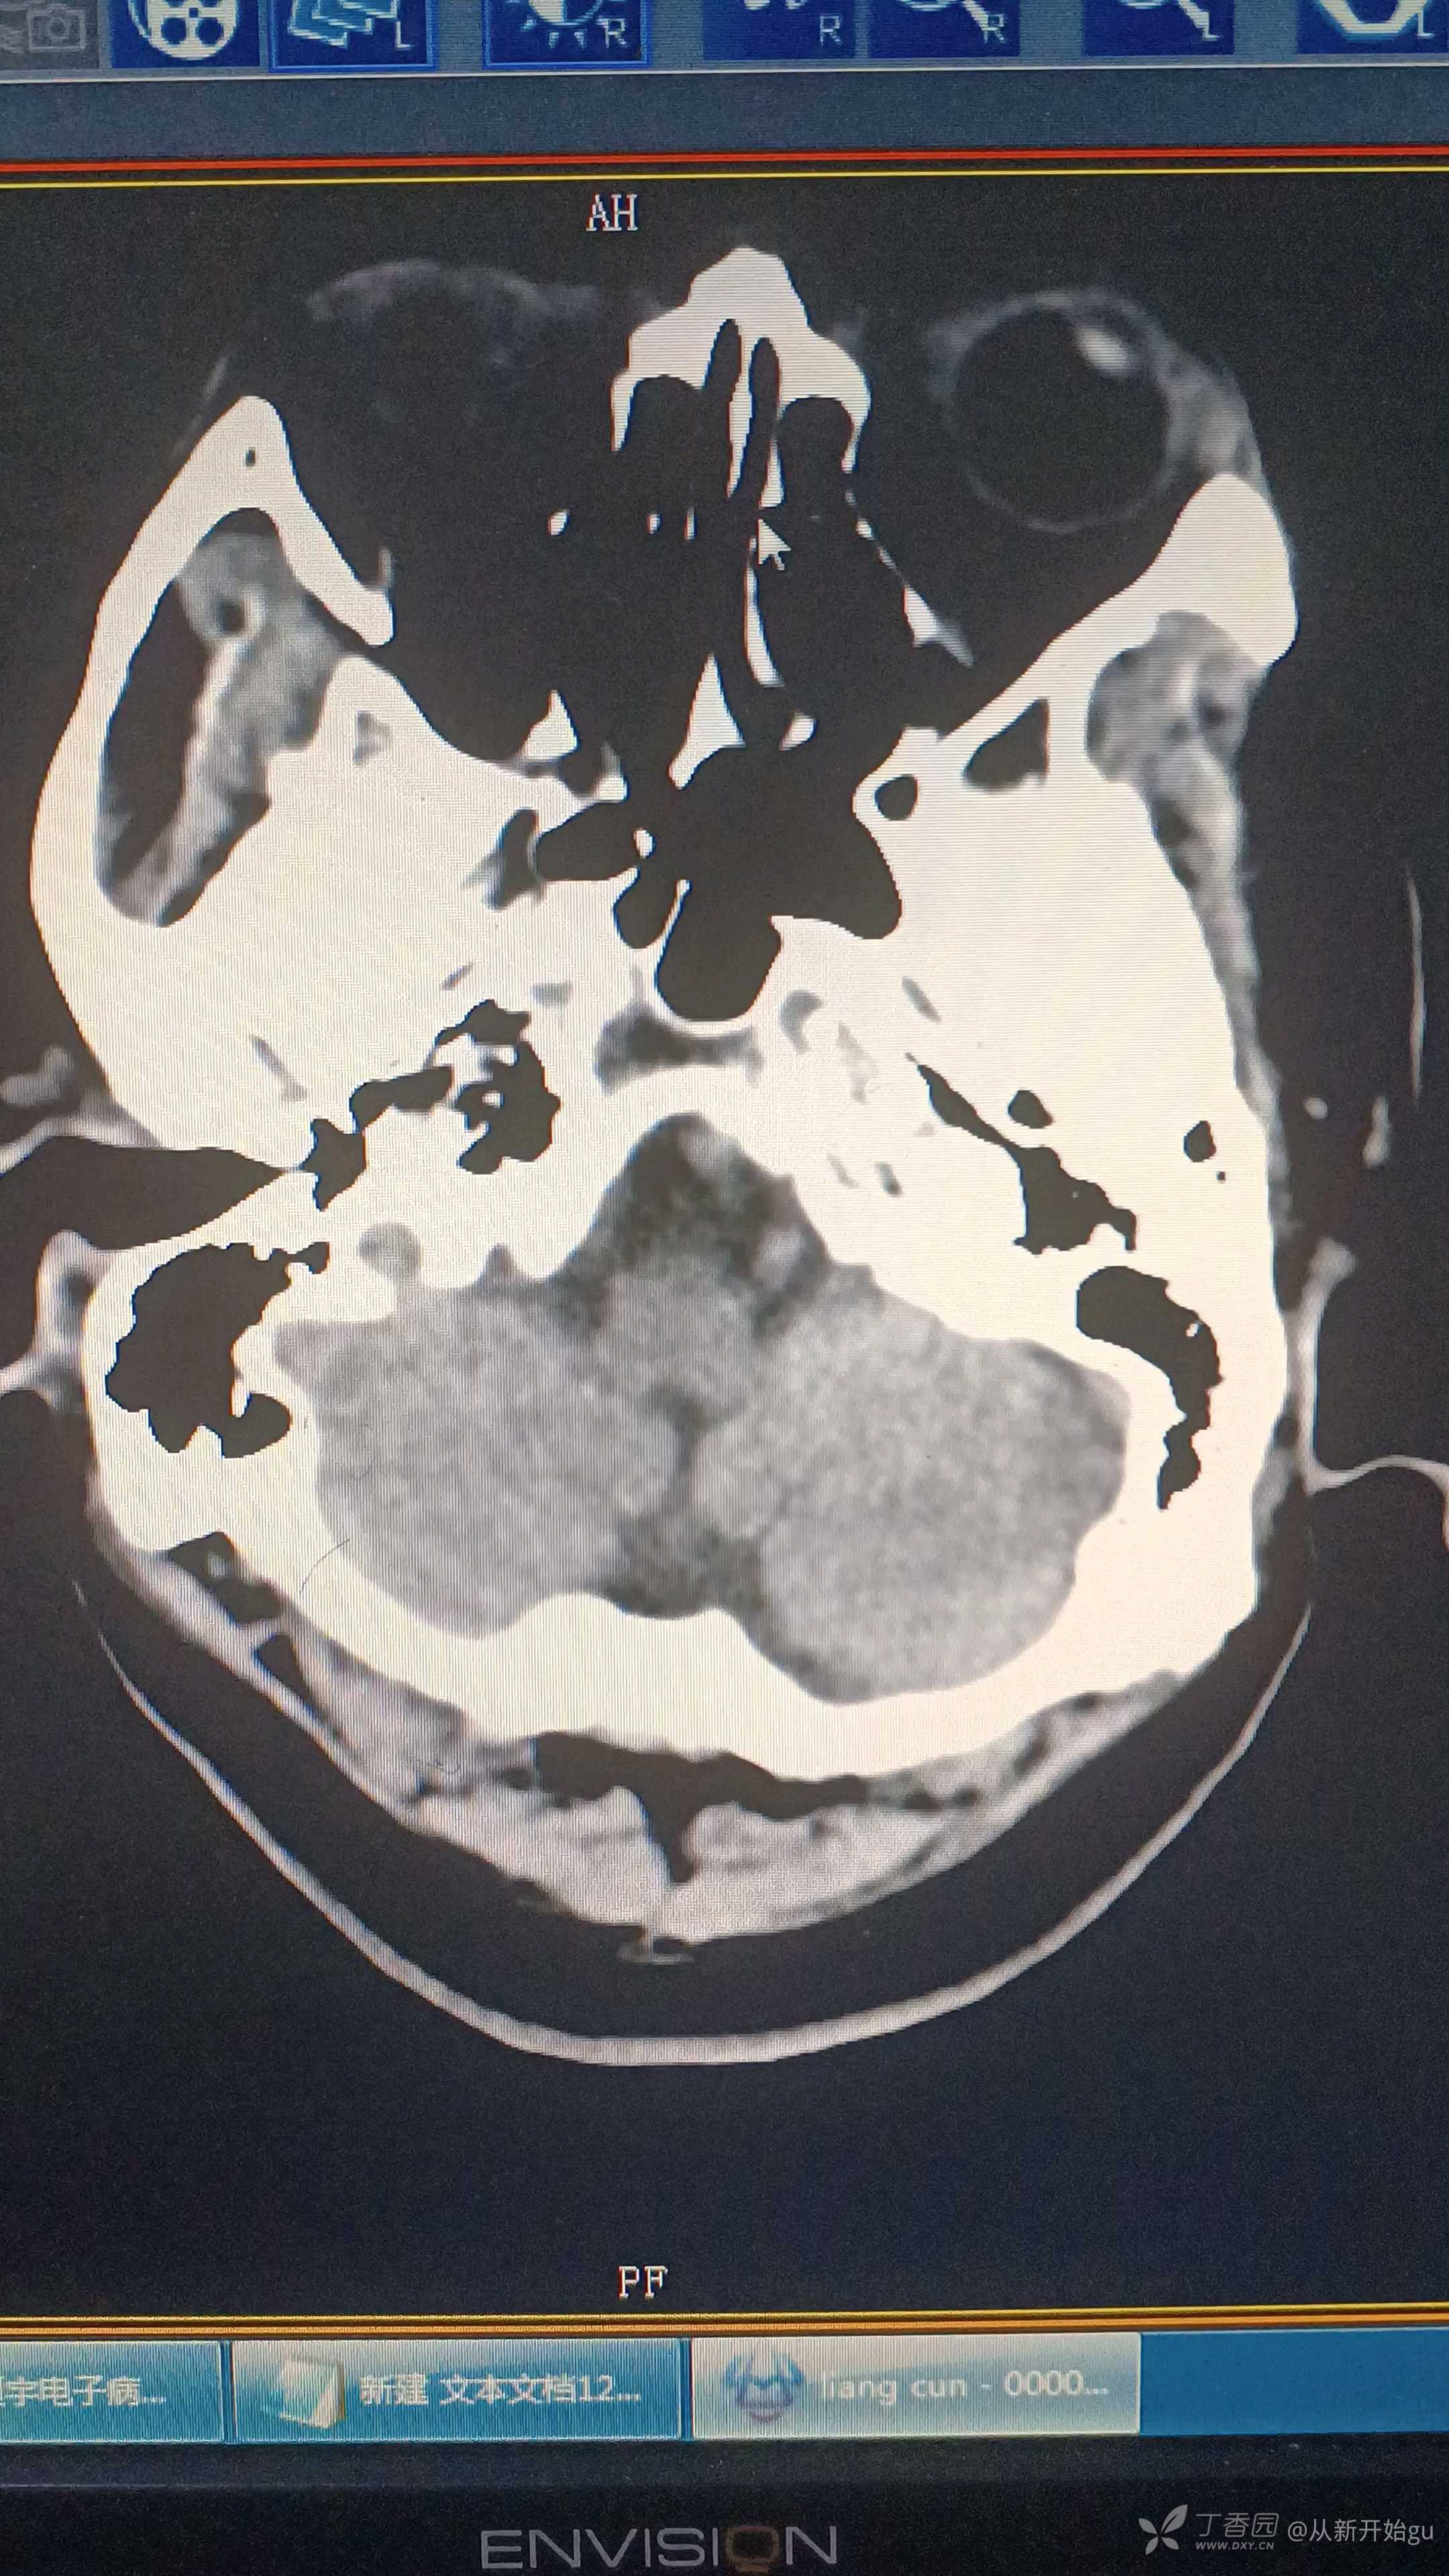

患者男,61岁,主因言语不利伴右侧肢体活动障碍2小时(醒后发现)。查体:轻度构音障碍,右侧鼻唇沟稍浅,不能配合神舌,右上肢肌力2级,右下肢肌力3级,右侧巴氏征阳性。既往高血压病史,冠心病病史,10天前因反应迟钝对症输液治疗,疗效差。这个病人的诊疗方案是?醒后卒中,颅脑CT如下……